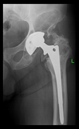

The radiological examination allowed us to verify the close bone-to-implant contact and the unchanged position of the implant during follow-up.

In all the cases operated with the above-described targeting procedure, the stems of the cups remained between the cortical bone surfaces without perforation of the linea terminalis, as shown by postoperative radiographs. There were no complicated surgical situations. In 16 cases, the wound healings were uneventful, and the hips were able to bear weight again after postoperative rehabilitation.

The only patient who suffered an infection healed after the removal of the implant. This complication rate is known and in line with accepted values.

One septic complication occurred. This complication rate is consistent with other revision techniques. In this case, the implant had to be removed, and the patient remained in Girdlestone condition. In such cases, removal of the implants and, of course, surgical debridement and antibiotic treatment are essential. The condition after resection is called Girdlestone’s condition. We had no other complications or unexpected outcomes.